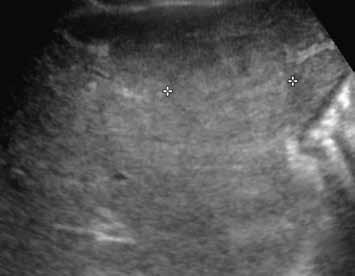

V UZ jsou patrná vícečetná izoechogenní ložiska (1, 2). U jiného pacienta (3) vidíme v játrech převážně hypoechogenní ložiska (žluté šipky) s naznačeným hyperechogenním periferním lemem (červené šipky). Po aplikaci kontrastní látky se ložiska patrná na obr. 1, 2 homogenně sytí a ani téměř po třech minutách nedochází k jejich vymývání (4–6).

Přívodná tepna má rezistenční index (RI) nižší, než je v arteria hepatica či jejích větvích (v průměru o 0,19). Někdy vidíme na periferii velkou drenážní žílu. V nativním CT obraze je FNH izodenzní nebo mírně hypodenzní a homogenní (obr. 4). Na MR je ložisko izointenzní nebo hypointenzní v T1-váženém obraze (94–100 %) (obr. 5), mírně hyperintenzní nebo izointenzní v T2-váženém obraze (94–100 %) a homogenní (96 %).

Nativně je v játrech ložisko, které je na CT hypodenzní (4), na MR izointenzní (5).

Na CEUS je v arteriální fázi patrný v levé polovině obrázku typický centrifugální charakter sycení ložiska, které je vidět v pravé polovině obrázku v B -módu (jako hypoechogenní) (6–8). Na CT (9) i MR (10) se ložisko (z obr. 4, 5) sytí homogenně, vyjma centrální vazivové jizvy, která zůstává hypodenzní.